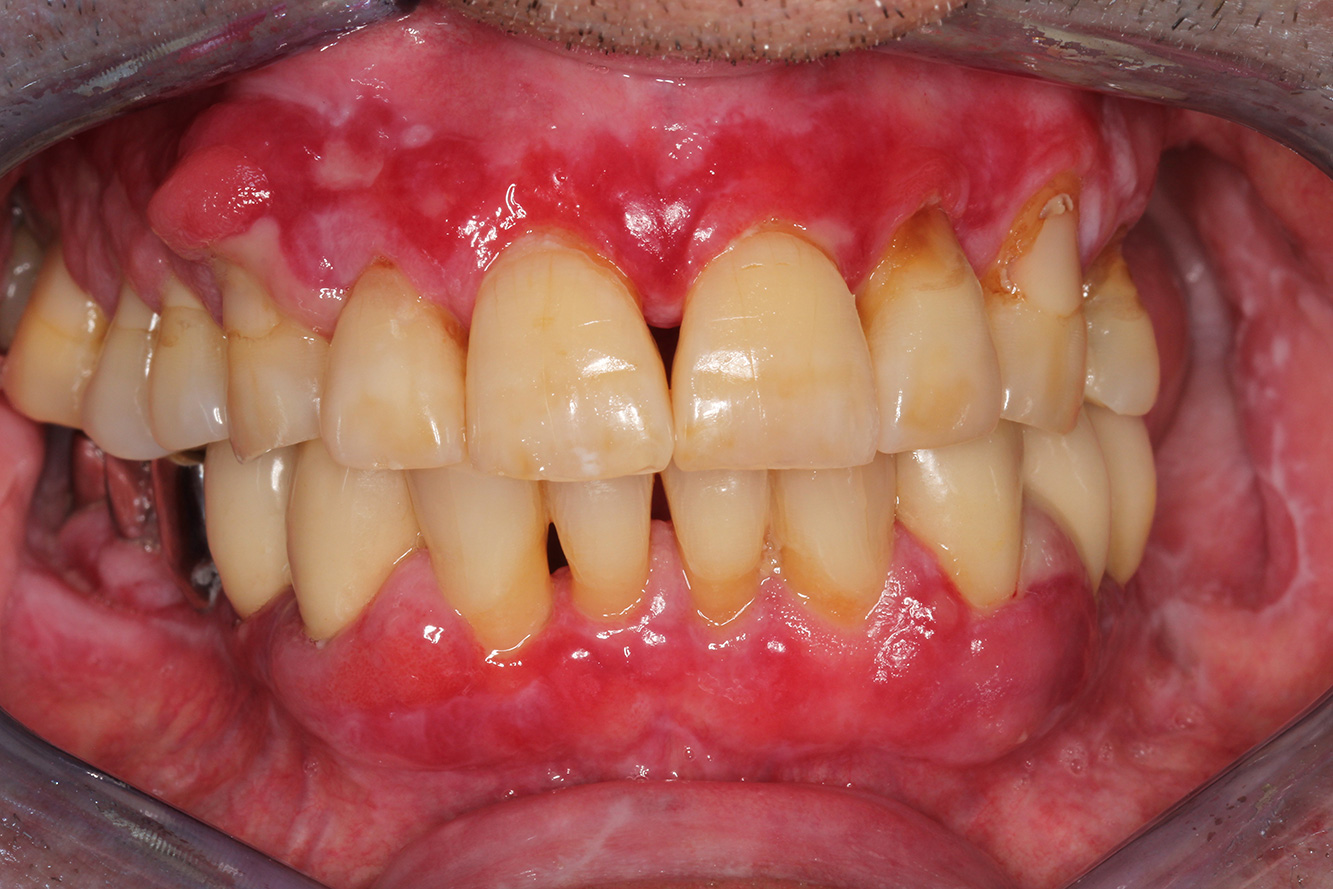

Paciente de trasplante con hiperplasia gingiva

Se presenta un paciente de 71 años con trasplante de riñón e hipertensión (presión arterial alta). Debido a su historia médica, es necesario el tratamiento continuo con ciclosporina para suprimir el sistema inmunitario y amlopidina para bajar la presión arterial. Además, el paciente relata encías sensibles y sangrantes. Desde el punto de vista de la salud oral, hay dientes restaurados con ocho piezas faltantes, hiperplasia gingival pronunciada, periodontitis en fase II, de grado B con bolsas activas y una caries inicial en la pieza 22. En la evaluación del riesgo de caries se ha establecido un riesgo de caries medio (API 60). Para la sesión de profilaxis se hacen las siguientes recomendaciones. más información